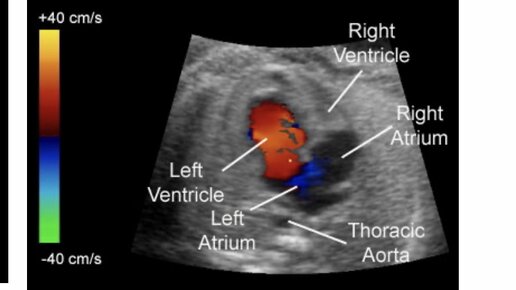

Здравствуйте! Я врач ультразвуковой диагностики, специализируюсь на пренатальной диагностике, также являюсь врачом акушером-гинекологом с большим стажем работы. Меня зовут Марина Багдасарян.  В сегодняшней статье мы обсудим возможность и необходимость проведения допплерометрии на первом скрининге. На первом скрининге я уже упоминала на что необходимо обратить внимание и говорила, что важно в этом сроке оценить структуры сердца насколько это возможно. Потому что, большие пороки развития сердца и главных сосудов уже можно диагностировать на первом скрининге...